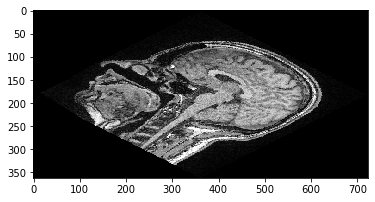

Translation d’images avec clesperanto#

clesperanto suit le système ZYX, et les matrices de transformation affine sont généralement écrites sous la forme suivante. Veuillez noter que dans le système dit ZYX, le vecteur de translation se lit x-y-z de haut en bas.

cle_transformed = cle.affine_transform(image, transform=matrix)

cle.imshow(cle_transformed[100])